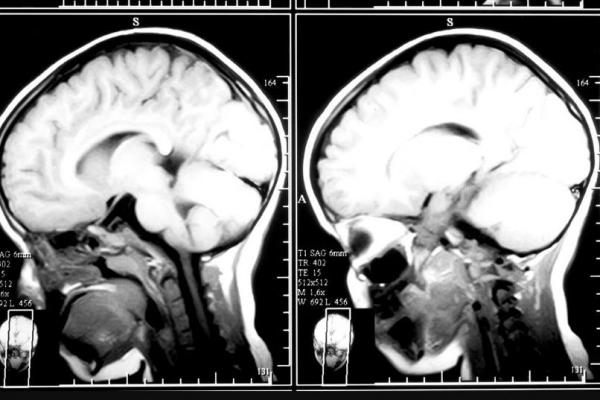

La comprensión de las estructuras químicas y anatómicas que intervienen en cada uno de los procesos dentro del campo de la salud y también de los trastornos mentales, aporta una visión

global necesaria para el verdadero dominio en el discernimiento del ser humano.